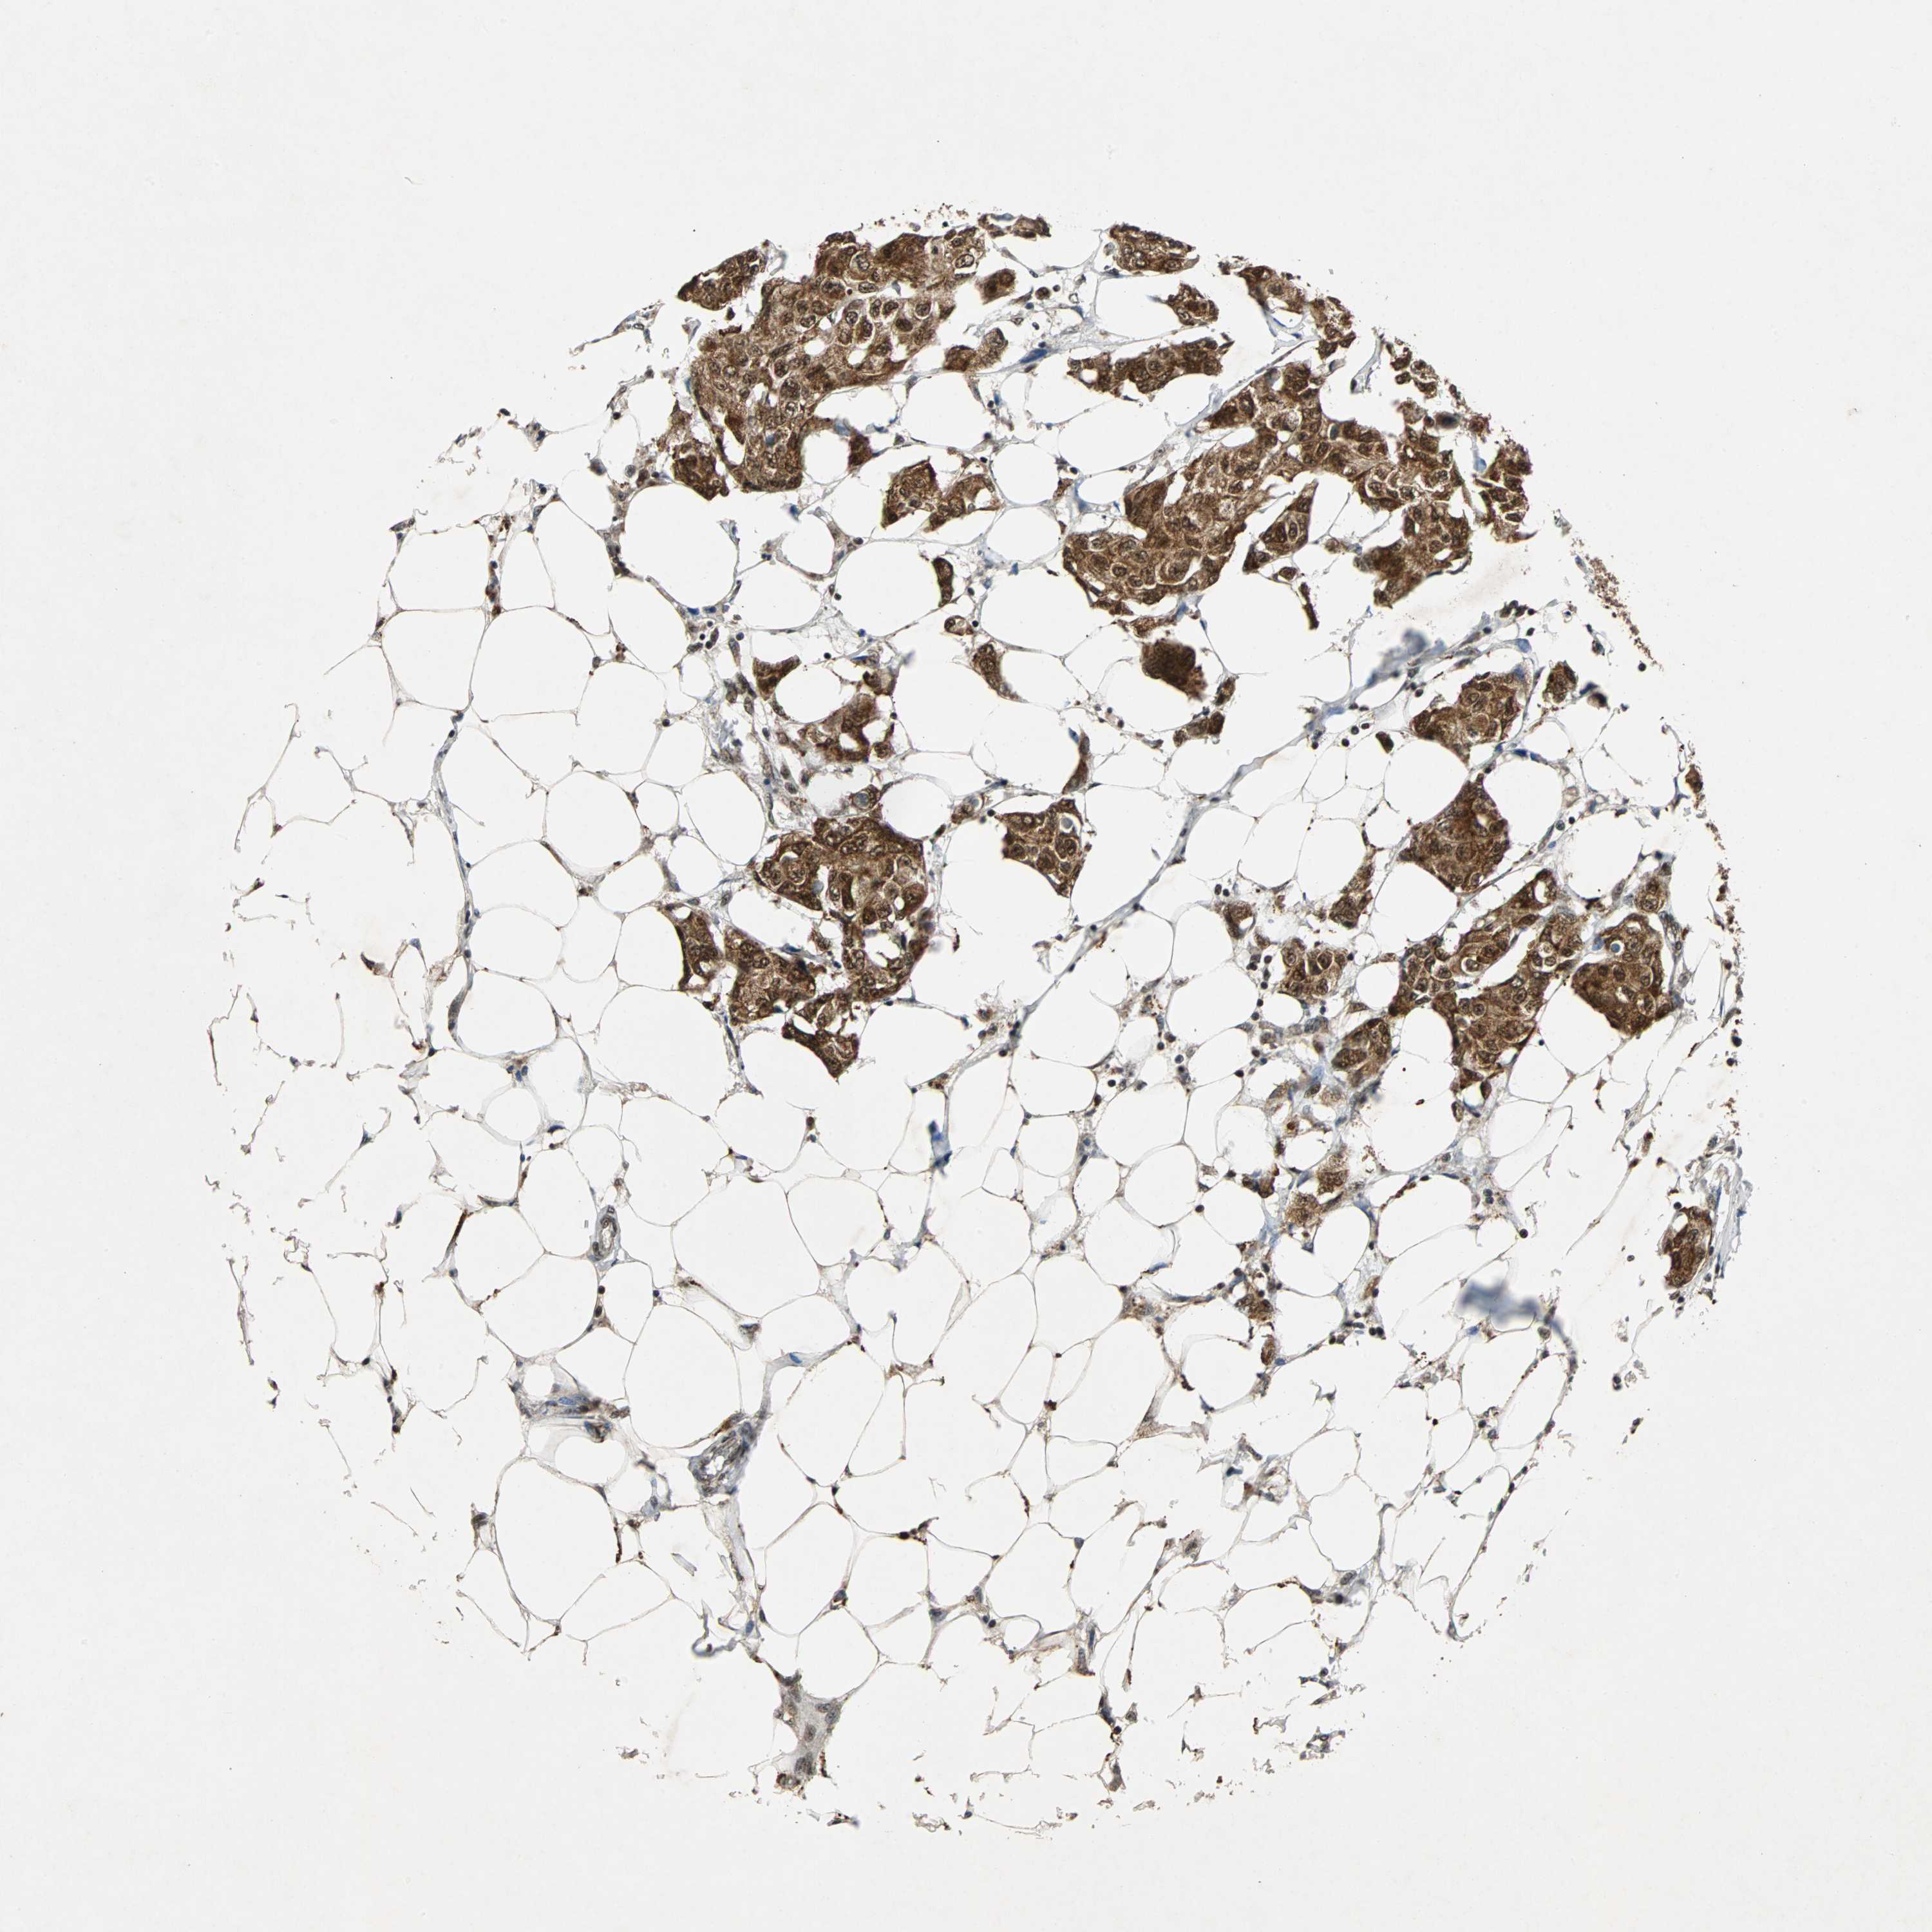

BRCA TCGA BRCA VALIDATION PROTEIN EXPRESSION

ANTIBODIES

AND

VALIDATION